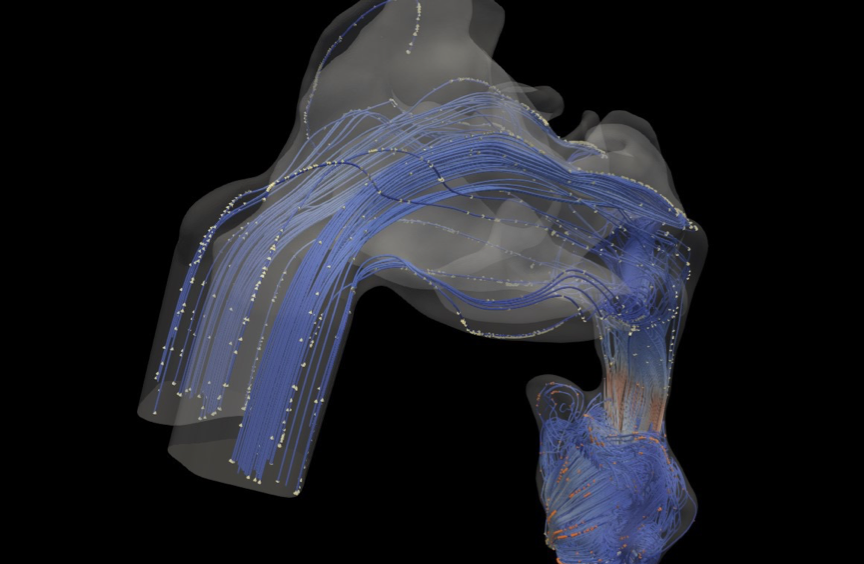

Fig 4. CFD simulation results illustrating velocity streamlines and dispersed particles at various sections of the upper airway.

• Velocity Magnitude and Jetting: High-velocity jets of air form just downstream of the narrowest part of the airway. Visualizing this jet helps pinpoint the precise location and severity of the collapse.

• Turbulent Kinetic Energy (TKE): This quantifies the intensity of turbulence. High TKE is often associated with the site of obstruction and a source of loud snoring or flow limitation.